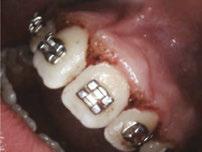

Dr. Bill Waggoner discusses the benefits of using liners along with a case presentation from Dr. Paul Bahn

Cavity liners and indirect pulp capping (IDPC) materials have been used in dentistry for decades. The recent introduction of NuSmile’s NeoLINER™ LC now provides one of the most therapeutic, easy-to-use liners on the market! It is a light-cured MTA-modified bioactive material that is recommended for use as either a cavity liner or as an indirect pulp-capping material. For decades, calcium hydroxide was the most popular lining or indirect pulp-capping material, primarily because of its ability to stimulate reparative dentin. However, its solubility after placement was found to be a problem. Zinc oxide and eugenol, glass ionomers, and resin-modified glass ionomers have also been used as liners, bases, and IDPC materials, but each has shortcomings.

Liners are materials that are placed in thin layers over exposed dentin in the deepest portion of cavity preparations. They function to seal dentin tubules, prevent microleakage, provide some thermal insulation, and depending on the material used, stimulate the formation of reparative or tertiary dentin. Historically, indirect pulp-capping materials have been used when a thin layer of carious dentin remains after deep excavation with no exposure of the pulp and no clinical signs of irreversible pulpitis. In recent years, indirect pulp capping in pediatric dentistry has been utilized when larger amounts of carious tissue remain, but the caries can be sufficiently sealed from the oral environment with a full coverage restoration like a stainless steel or zirconia crown. The main goal of both liners and IDPC materials is to minimize inflammation, promote healing, and maintain vitality of the dental pulp. Indirect pulp capping materials may also demonstrate some bactericidal properties to kill any remaining bacteria that may remain.

The MTA in NuSmile’s NeoLINER LC provides a continuous high calcium release. This, in combination with a high pH, promotes hydroxyapatite formation and protects against hypersensitivity. The high pH also has bactericidal effects to reduce remaining bacteria. NeoLINER LC is packaged in a syringe with 27-gauge disposable tips that allow for precise and easy placement. Its viscosity ensures it will stay in the area where it is placed until it is cured with a curing light. NeoLINER LC is

moisture tolerant, has low water solubility, and is compatible with all etching, bonding, and resin restorative materials. It’s also radiopaque for easy postoperative assessment.

While it is an excellent liner and IDPC material, NeoLINER LC is not recommended for direct pulp capping because of its resin component which can act as an irritant. Any materials containing a resin can damage or kill pulpal tissue if placed in direct contact. If a pulpal exposure is realized, a resin-free MTA material such as NuSmile’s NeoMTA® 2 or NeoPUTTY® is recommended as a direct pulp-capping agent due to its exceptional biocompatibility. These MTA materials, which have a delayed set, may be covered with NeoLINER LC for placement of an immediate final restoration.

Figure 1: Preoperative periapical radiograph of tooth No. 30 with a large radiolucent lesion approximating the distal pulpal horn and a smaller radiolucent lesion closer to the mesial marginal ridge Figure 3: Conservative removal of all carious dentin on all axial walls and pulpal floor. No clinical pulpal exposure noted, but likely very close to distal buccal pulp horn Figure 2: Large active carious lesion involving the entire distal buccal cusp and surrounding aspect of tooth No. 30. Smaller Class VI lesion located on the mesial lingual cusp on No. 30 Figure 4: Placement and curing of two separate thin layers of NeoLINER over the dentin. Image depicts the NeoLINER following the indirect pulp cap of tooth No. 30